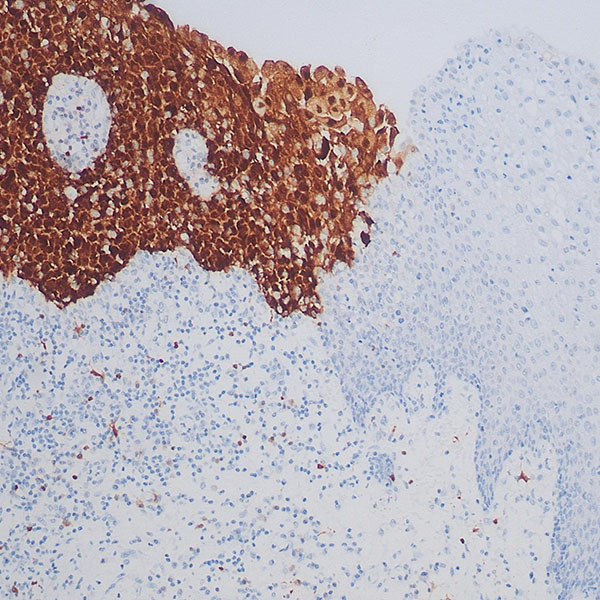

- 东极生物带你深入探索免疫荧光检测技术